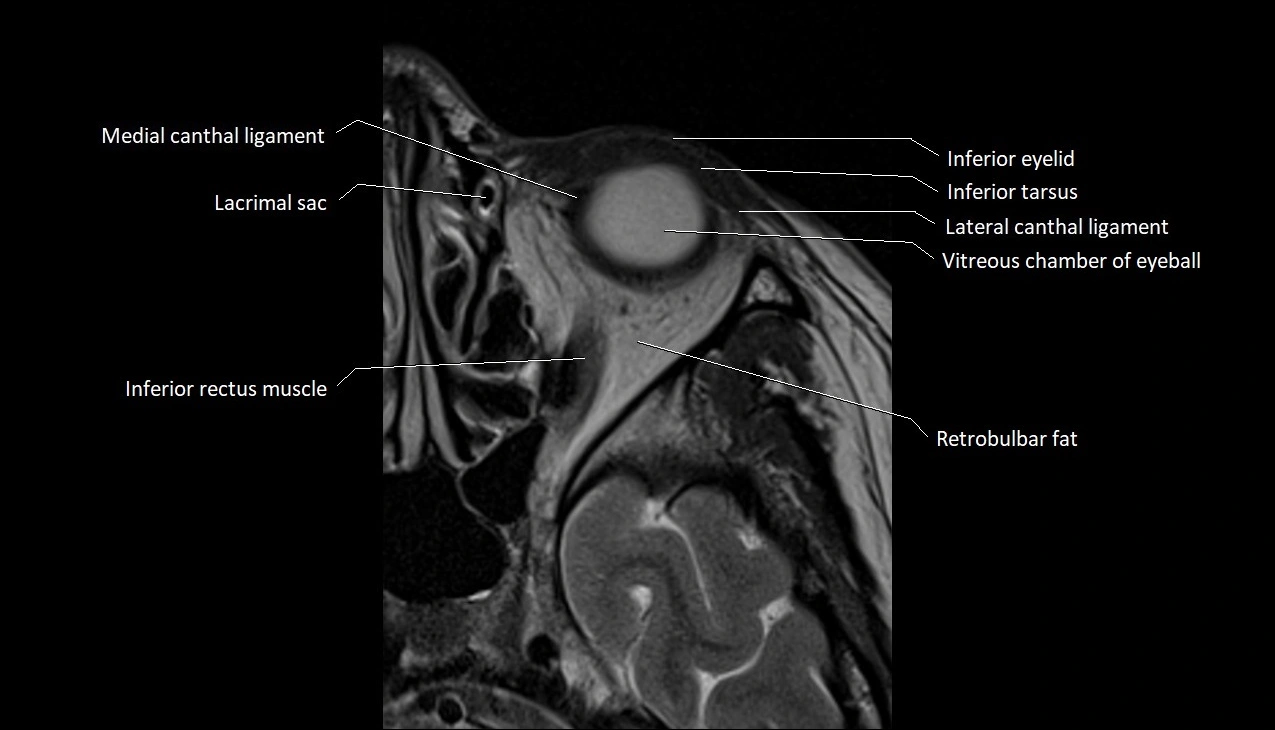

- Medial canthal ligament

- Lacrimal gland

- Inferior eyelid

- Inferior tarsus

- Lateral canthal ligament

- Vitreous chamber of eyeball

- Inferior rectus muscle

- Retrobulbar fat